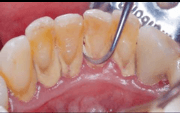

Yeme, içme ile oluşan yiyecek artıkları yani bakteri plağı, 1-2 gün gibi kısa bir sürede bile fırçalanmadığında, gingivitis dediğimiz diş etlerinde hafif, geçici kızarıklığa ve kolay kanamaya neden olur. Bu yumuşak hamur kıvamındaki birikintiler tartar denilen diş taşına dönüşmeden en kısa sürede düzenli ve etkili fırçalanır ise kısa sürede düzelecektir. Fırçalamaya ilave diş ipi ve gargara kullanımı, hijyen etkinliğini arttıran faktörlerdir.Fakat hem düzensiz hem uzun süre fırçalamama yada etkili olmayan (diş plağını uzaklaştıramayan) bir fırçalama ile bakteri plağı tartar dediğimiz daha sert bir yapı olan diş taşına dönüşürse, artık bu diş taşlarını, fırçalama ile uzaklaştıramayız. Bir diş hekimine gitmemiz gerekir.

Biz diş hekimleri, diş minelerinin zarar görmeyeceği teknikler ile diş eti hizasındaki diş taşlarını temizleriz. Aksi takdirde, diş yüzeyini değil tartar yüzeyini fırçaladığımız için yapılan işlem gerekli faydayı sağlamaz. Periodontitis dediğimiz daha ileri diş eti hastalığı olan bu durumda, diş taşı yüzeyi devamlı bakteri tutulumu yapar. Potansiyel enfeksiyon kaynağı oluşturur. Öncelikle diş etlerinde şişlik ve kolay kanamalar oluşur. Plak, diş taşına dönüşür ve diş eti oluşan tartar nedeni ile diş kök yüzeyine sağlıklı ve iyi tutunamaz, giderek diş eti çekilmeye başlar, diş aralarında boşluklar oluşur.Diş eti çekilmesi ile kök yüzeyi açığa çıkar.Açığa çıkan kök yüzeyinde soğuk, sıcak, tatlı hassasiyeti gibi yeme içme konforunun kaybı ile karşılaşırız. Ayrıca kolay kanayan enfektif diş etlerinde oluşan ağız kokusu da hastaların en çok şikayet ettiği diğer bir sorundur. Diş eti kanamalarına, düzenli ve etkili diş fırçalanmaması sonucu oluşan diş eti hastalıkları dışında; ergenlik, hamilelik, menopoz vb. hormonal değişiklikler, devamlı ilaç kullanımına bağlı tükürük salgısının azaldığı durumlar ve bazı sistemik hastalıklarda neden olabilmektedir.